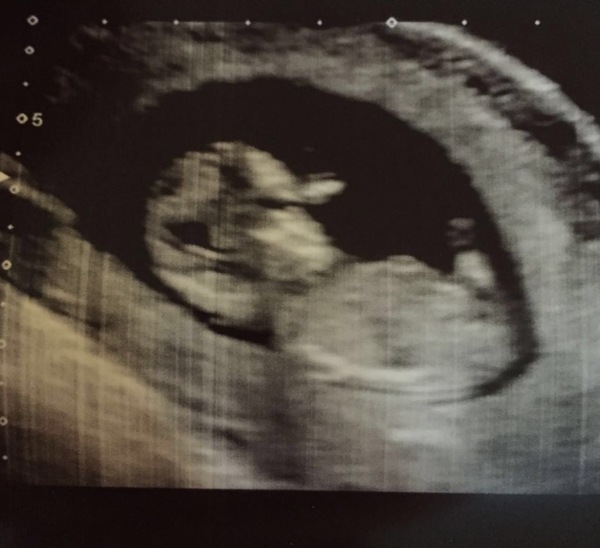

Thanks all scan went really well! Baby was fast asleep and MW couldn't get him to wake up at all at first (he/she was in wrong position to measure nuchal fluid) but when she eventually go them moving I was amazed at how much they wiggled and bounced around - didn't expect to see them move around so much at all for some reason! Was very surreal and amazing! Still finding it a very abstract concept that that wiggly snowman like thing is inside me and will one day be an actual baby?! Like, how did that happen??!!WinkGrin Potato seeing as you've asked I've attached scan pic, although don't think it's a a very good one! Plus they look like Pinocchio as hand up by face!!

Marmite this is how addled my brain is but I was just about to type "don't worry about the baby show, I'm sure there's another one in October" .... good grief, baby brain is a thing! Gorgeous scan! I love 12 week scans, congratulations! 🌹